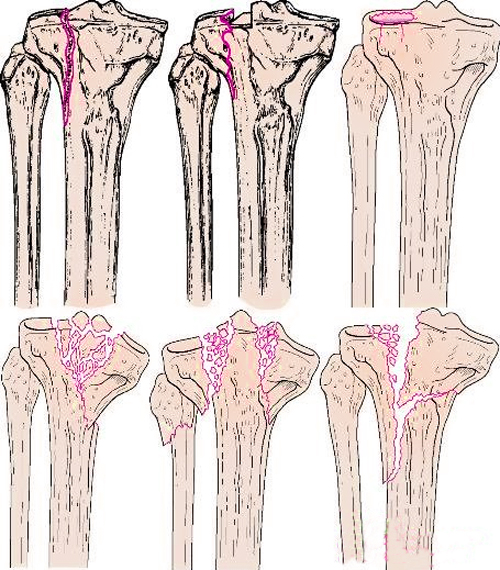

Большая берцовая кость состоит из бугристости, мыщелков и нижней части, соответственно и переломы этой кости бывают разными.

Перелом мыщелков берцовой кости может быть как одиночный, так и двойной. Такая травма является следствием приземления или падения на прямые ноги с большой высоты на голень. Проблематично и то, что такой перелом берцовой кости обусловлен кровоизлиянием из мыщелков в сустав колена. Лечение такого перелома при повреждении мыщелков производят путем наложения гипса, а также обезболивания. Процесс восстановления занимает от 1 до 2 месяцев. Если обнаружено смещение, то применяется специальная технология репозиции и процесс восстановления существенно затягивается.